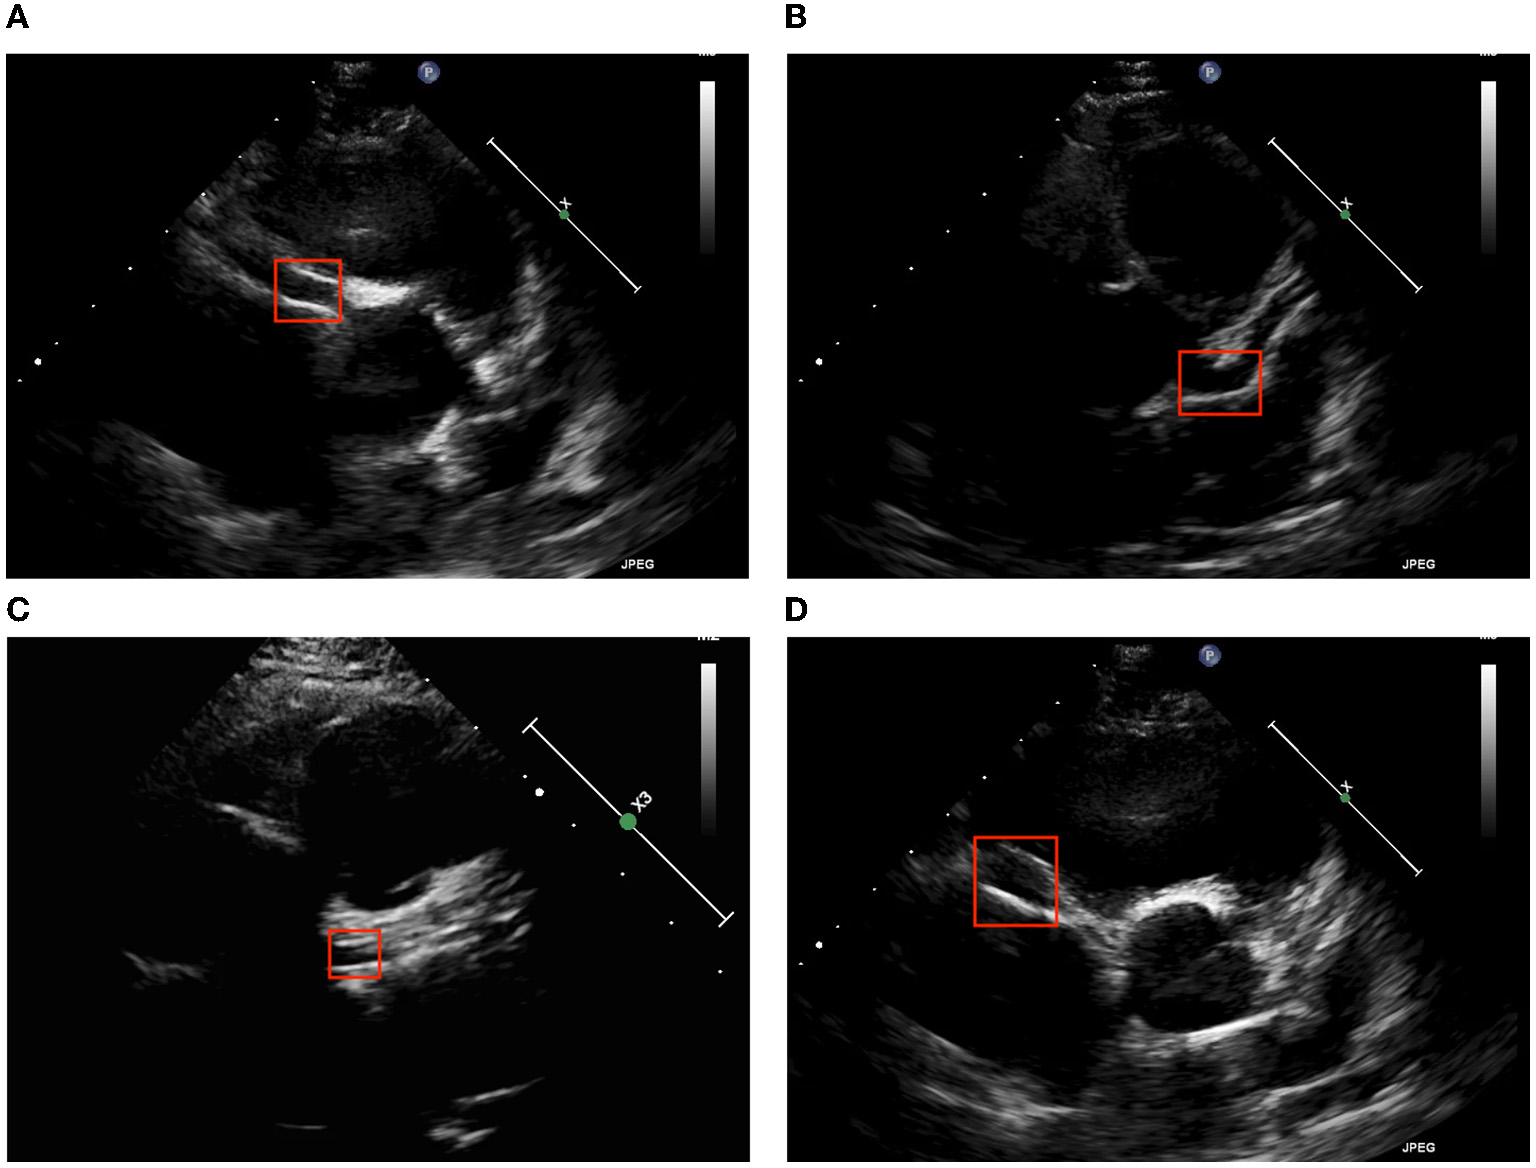

Coronary arteries can be divided into left coronary arteries (LCAs) and right coronary arteries (RCAs). One of the main symptoms of KD is CLs, which are detectable on cardiac ultrasound. Clinically, short axis ultrasound can be used to assess for abnormalities in LCAs and RCAs. Figure 2 presents ultrasound images from Kaohsiung Chang Gung Hospital; we took two features of CLs, brightness and dilatation (10), to be detected.

Figure 2

Two major echocardiographic coronary patterns in children with KD. (A) LCA brightness, (B) LCA dilatation, (C) RCA brightness, and (D) RCA dilatation.

The four patterns also have different difficulty levels. LCA dilatation has the better detection result from no matter which object detection algorithm is applied. However, the performance of the brightness pattern of LCA and RCA is poor. The primary reason is that the characteristic of dilatation shows that the color inside the vessel is black and white outside the vessel. However, the brightness pattern is the grayish white of the vessel wall compared to the grayish color in the background. As a result, the brightness pattern is harder to detect.